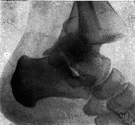

1. The bone of the ankle that articulates with the tibia and fibula to form the ankle joint. Also called anklebone, astragalus.

(Anatomy) the bone of the ankle that articulates with the leg bones to form the ankle joint. Nontechnical name: anklebone

the uppermost bone of the proximal row of bones of the tarsus; anklebone.

The bone that forms a joint with the tibia and fibula, making up the main bone of the ankle. See more at skeleton.

2.talus - the bone in the ankle that articulates with the leg bones to form the ankle jointtalus - the bone in the ankle that articulates with the leg bones to form the ankle joint

ankle, ankle joint, articulatio talocruralis, mortise joint - a gliding joint between the distal ends of the tibia and fibula and the proximal end of the talus